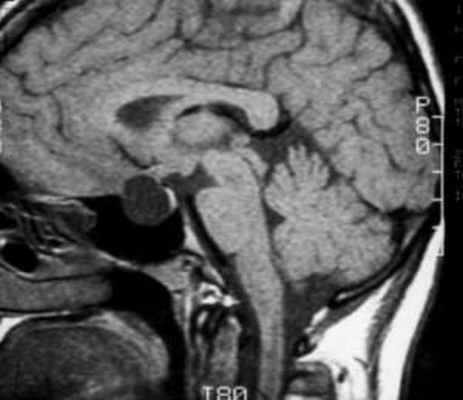

В ходе лабораторного обследования показатели общего анализа крови и мочи в пределах референсных значений, отмечено некоторое снижение протромбинового времени до 9,4 сек (10–14), повышение протромбина до 169% (70–130), общего холестерина до 5,87 ммоль/л (3,3–5,2). В гормональном анализе крови на фоне приема каберголина в дозе 0,25 мг в неделю – уровень пролактина 932,8 мЕд/л (90–540). По данным МР-томографии головного мозга в хиазмально-селлярной области подтверждено наличие объемного образования размерами 12*15*15 мм с выраженным кистозным компонентом и супраселлярным распространением (хиазма интактна). Учитывая ряд специфических признаков, специалистами отделения магнитно-резонансной томографии верифицирована киста кармана Ратке (рис. 2).

Рис. 2. Динамика объемного образования гипоталамо-гипофизарной области (А, Б – 2009 г., В, Г – 2011 г., Д, Е – 2015 г.).